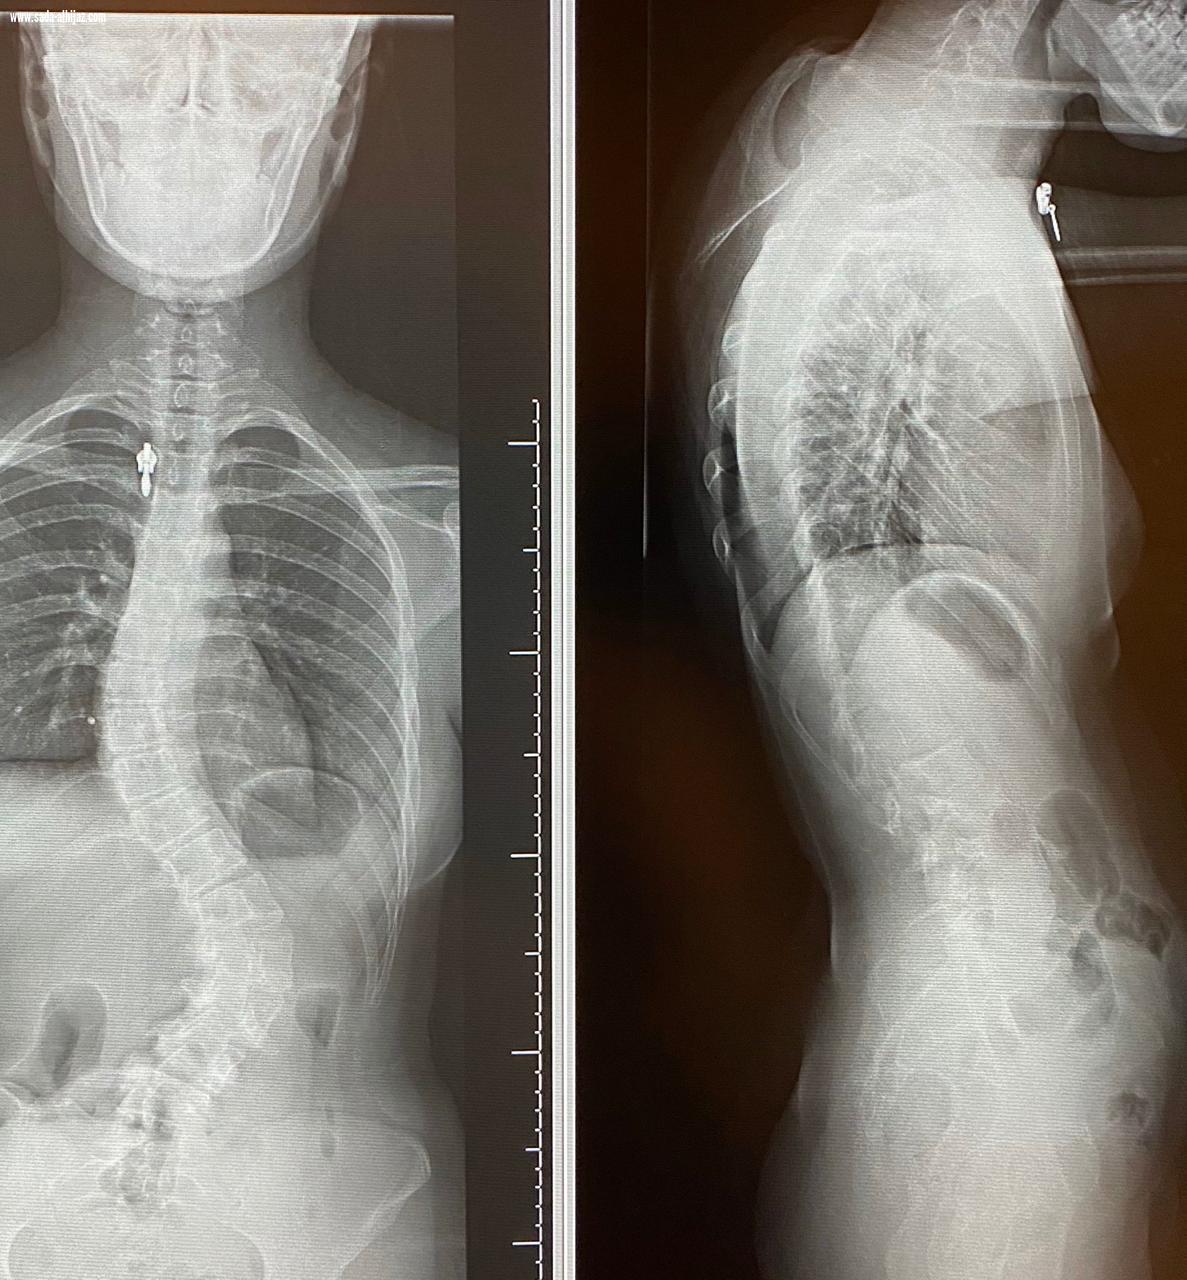

إنهاء معاناة مريضين من إنحناء للعمود الفقري في بيشة

بيشه .عيد البيشي تمكن بفضل الله المشرف العام على مستشفى الملك عبدالله ببيشة الدكتور صالح آل خبتي استشاري جراحة العظام وجراحة العمود الفقري إنهاء معناه مريضين من انحناء العمود الفقري بإجراء عمليتين جراحيه تكللت بالنجاح . الجدير بالذكر أن مستشفى الملك عبدالله في بيشة يعد واحد من الصروح الطبية على مستوى المنطقة، وهو مستشفى مرجعي وتبلغ سعته السريرية ٣٦٥ سرير، ويضم جميع التخصصات والأقسام الطبية المختلفة.